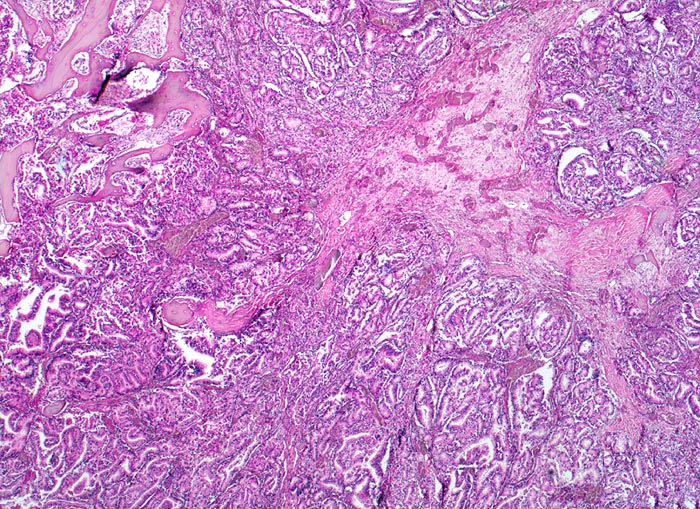

Prostatakarzinom: Knochenmetastase

Knochen, Wirbelsäule

Grösseres Infiltrat eines Adenokarzinoms mit dos à dos liegenden Drüsenschläuchen. Areal mit Granulationsgewebe und kleinen Knochenresten.

Bei Autopsie finden sich zahlreiche, teils osteoplastische, teils osteolytische Metastasen im Bereich der Wirbelsäule. Die Karzinomdrüsen sind immunhistochemisch positiv für Prostata spezifisches Antigen.

Bekanntes metastasierendes Prostatakarzinom. St.n. bilateraler Orchiektomie. Diffuse Schmerzen im Bereich der Wirbelsäule. Der Patient verstirbt an einem Myokardinfarkt.